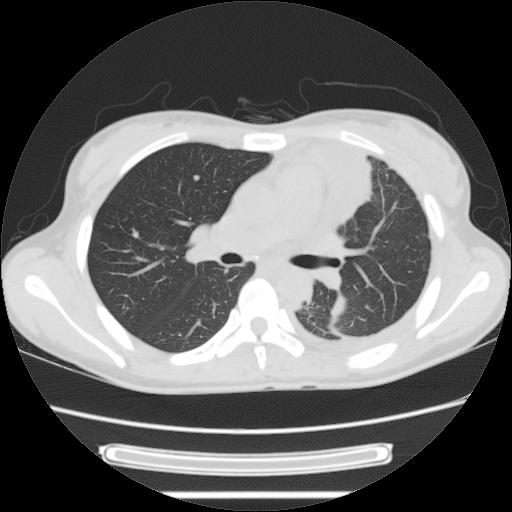

女,29岁,胸部不适,在外院胸片提示胸腔积液,到我院ct检查。

肺窗: